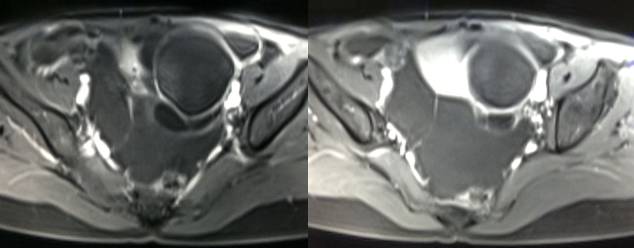

MR检查:

病理结果:黄体血肿

根据时间不同MR信号也有所不同,TIWI脂肪抑制序列能够鉴别脂肪和出血。

卵巢囊肿:呈均匀的T1WI 低信号,T2WI 高信号,边界清楚,壁薄,大多数病灶直径≤5 cm,但囊肿的起源及定性诊断困难。

巧克力囊肿:常呈多发的单囊或多囊改变,病灶大小不等,囊壁厚薄不均,囊内信号复杂,囊内或各囊腔间血液因出血时期不同,信号常呈多样性,囊肿内反复出血、破裂,形成相互粘连的多房性囊肿,是其较为特征性的表现。

在鉴别卵巢畸胎瘤、出血性囊肿或巧克力囊肿时,MR 脂肪抑制T1WI 可明确肿块内高信号成分是脂肪还是出血,同时由于脂肪组织与非脂肪组织的共振频率不同,在两者交界处沿磁场频率编码方向出现化学位移伪影,但出血性囊肿与巧克力囊肿的鉴别有时较为困难。